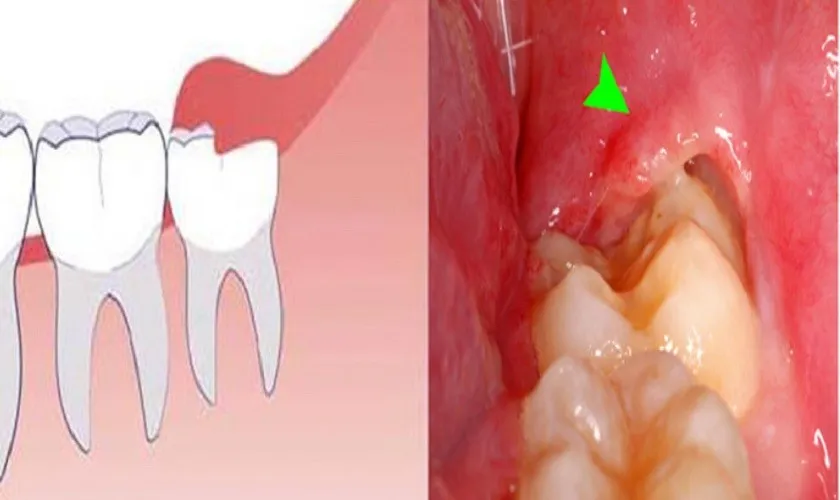

Khi răng khôn mọc lên ở vị trí không thuận lợi, rất có thể sẽ dẫn đến nhiều vấn đề khác nhau. Có những trường hợp mọc lệch, mọc ngầm hoặc thậm chí nằm hoàn toàn dưới nướu, gây ra những cơn đau và tình trạng viêm nhiễm liên tục. Qua đây, chúng ta cùng xem xét cụ thể hơn về các biểu hiện bất thường này.

Mọc lệch, mọc ngầm hoặc nằm dưới nướu gây đau, viêm tái phát thường xuyên

Khi răng khôn mọc lệch, nó không chỉ gây ra cảm giác đau nhức mà còn làm tổn thương đến các răng xung quanh. Điều này xảy ra do áp lực từ răng khôn có thể đè lên răng số 7, dẫn đến tình trạng xô lệch và hình thành khe giắt thức ăn. Với tình trạng này, việc vệ sinh răng miệng trở nên khó khăn hơn, tạo điều kiện cho vi khuẩn phát triển, gây ra tình trạng viêm nhiễm.

Khi răng khôn nằm ngầm dưới nướu, không thể mọc lên, nó có thể tạo ra áp lực đến chân răng, gây viêm nhiễm lợi và đau đớn cho bệnh nhân. Những triệu chứng như sưng nướu, đau nhức và khó chịu có thể tái phát nhiều lần, gây ảnh hưởng đáng kể đến chất lượng cuộc sống của người bệnh. Nếu để lâu, tình trạng này có thể dẫn đến viêm xương hàm và các biến chứng nghiêm trọng khác.